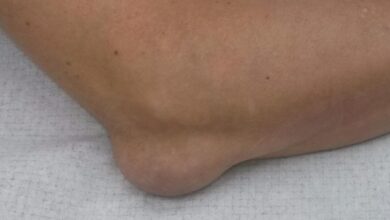

- Отек и утолщение сустава.